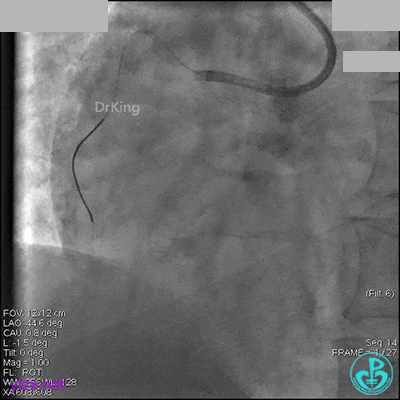

AL 1.0指引导管到位,简单短时尝试导丝不能顺利通过前降支或回旋支病变。改变策略处理右冠脉病变,计划植入2枚支架。AL指引导管到位,Sion blue导丝到达右冠脉远端。导丝通过后1.5mm及2.5mm球囊14~16atm充分扩张中段病变。

右冠脉中段充分扩张后欲植入3.5×38mm支架时,支架难以通过中远段扭曲处,且指引导管、导丝弹出飞扬。反复尝试导丝重新到达右冠脉远端时通过不顺利,局部造影剂滞留,远端血流接近3级。